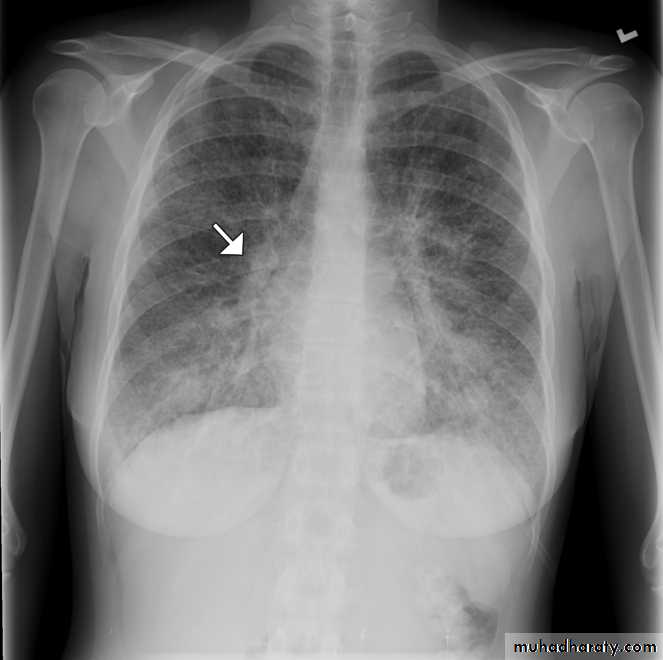

Chest radiography shows multiple pulmonary nodules of varying sizes consistent with metastatic cancer.

Multiple and bilateral secondaries

Chest radiography of a 31-year-old woman showing diffuse interstitial and septal thickening (arrow) in both lungs.